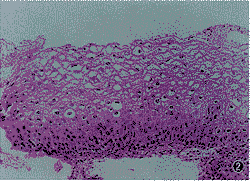

73例宫颈湿疣中,2例为尖锐湿疣,71例为扁平湿疣。根据核形态的差异,凹空细胞为Ⅰ型的有30例(图1,2),Ⅱ型的有43例(图3~6)。见表2。

图1 Ⅰ型凹空细胞核增大,核形不规则、染色深、结构不清,偶见双核。HE×300

图2 宫颈扁平湿疣伴CINⅠ,鳞状上皮增生、平坦,中表层可见Ⅰ型凹空细胞,基底层细胞轻度异型。HE×150

图 3Ⅱ型凹空细胞核增大、结构清晰,可见核仁,核膜不连续。HE×300

图4 Ⅱ型凹空细胞的畸形核。HE×150

图5 为图4中畸形核的放大(↑).HE×300

图6 Ⅱ型凹空细胞,核为底层细胞核的2~倍,可见双核、多核,伴病理性核分裂(↑)。HE×150

图7 鳞状上皮基底层出现CINⅠ,中表层可见Ⅱ型凹空细胞,伴病理性核分裂(↑)。HE×300